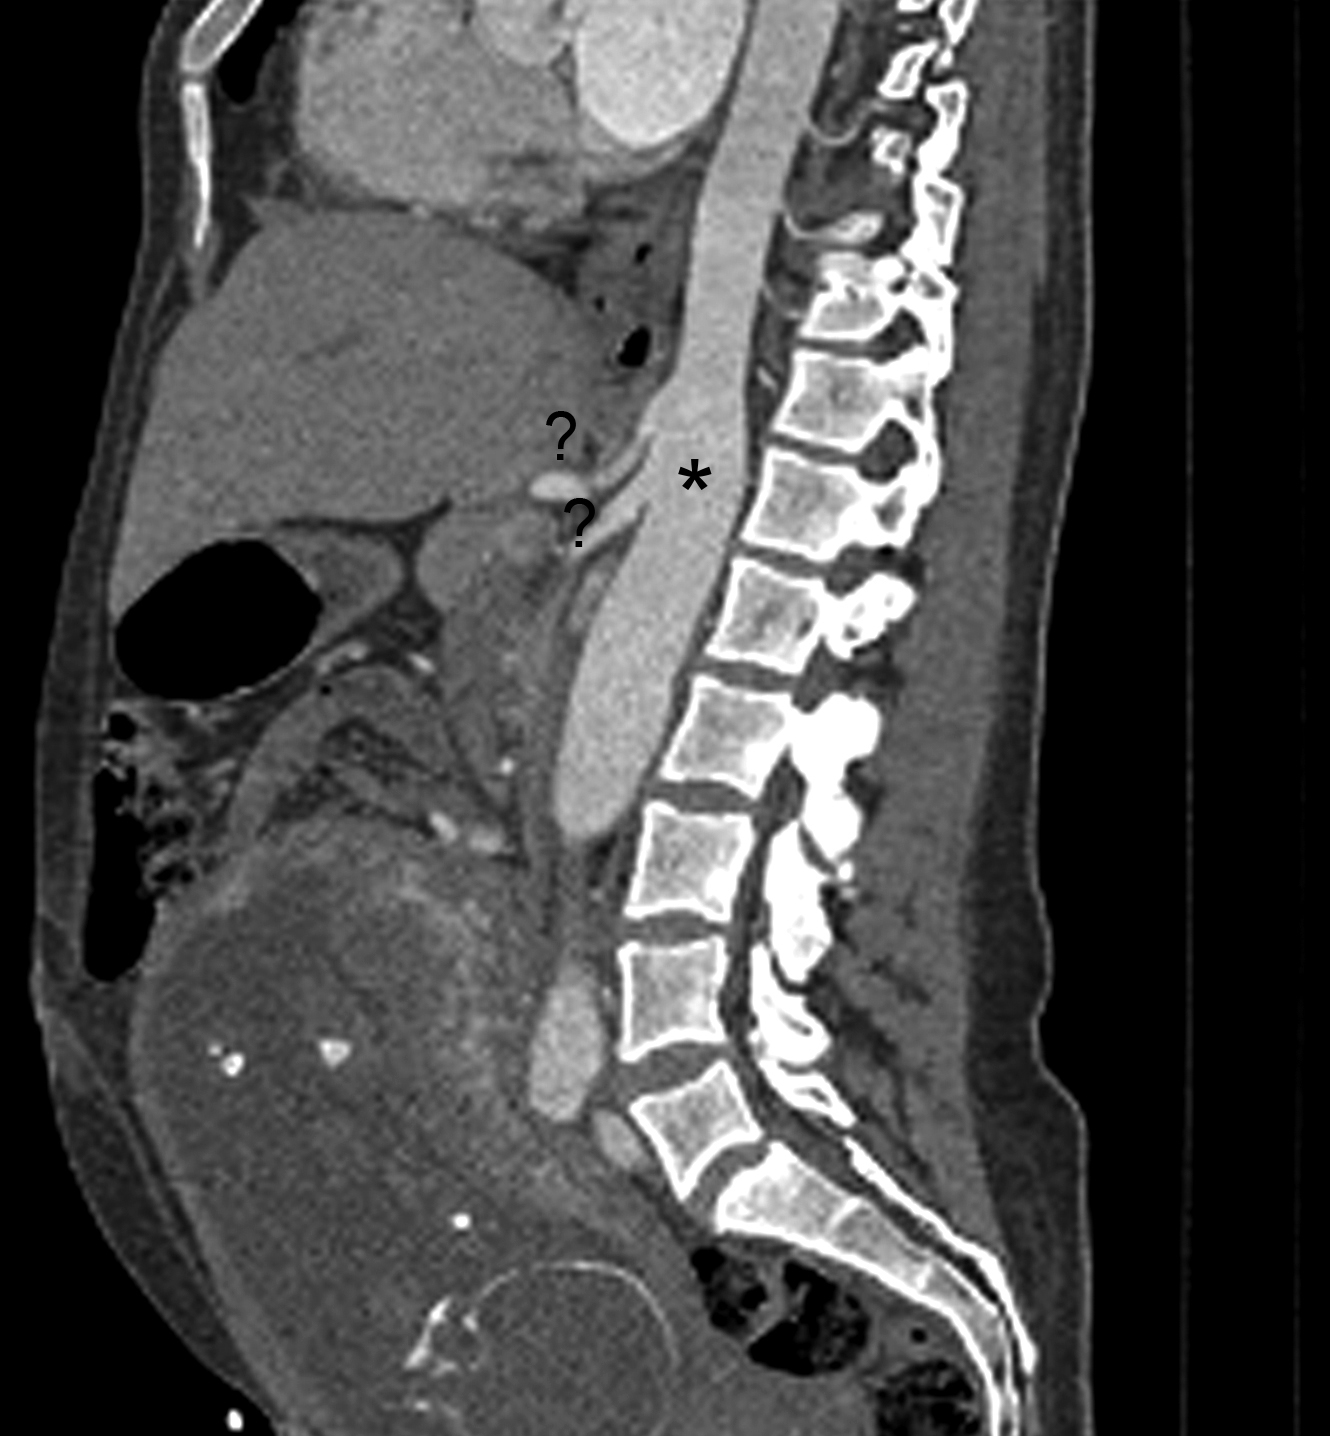

Figura 3

Angiografía de Aorta por TC Corte sagital. (*) Aorta abdominal, (?) Tronco celíaco, (?) Arteria mesentérica superior.

El tronco celíaco y la arteria mesentérica superior se encuentran permeables y de calibre habitual. Se identifica un origen alto de las ramas viscerales de la aorta abdominal, a saber, el tronco celíaco a la altura del espacio discal T11-T12, la arteria mesentérica superior a nivel del cuerpo vertebral de T12, la arteria renal derecha a nivel del espacio T12-L1 y de la arteria renal izquierda a nivel del margen superior de cuerpo de L1. (Fig. 3)